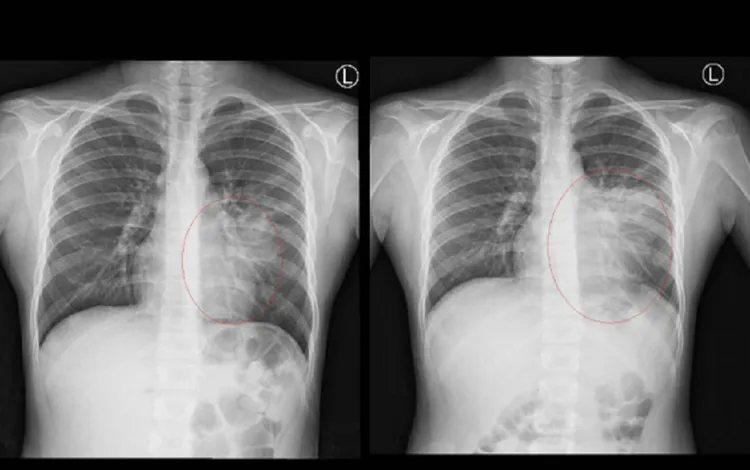

馬瑞杉說,女童轉院來之後,經多病原核酸檢測(PCR)確診是黴漿菌感染,而且其X光片左肺大片反白,顯示為肺炎,因此住院以常規的巨環類抗生素治療,但高燒仍未退,住院3天後的左肺X光片反白範圍更大了,顯示抗生素失效,改用替代的去氧羥四環素 (doxycycline)治療才好轉。

女童住院時X光片(左),接受抗生素治療3天後,X光片反白範圍更大(右)。彰化醫院提供